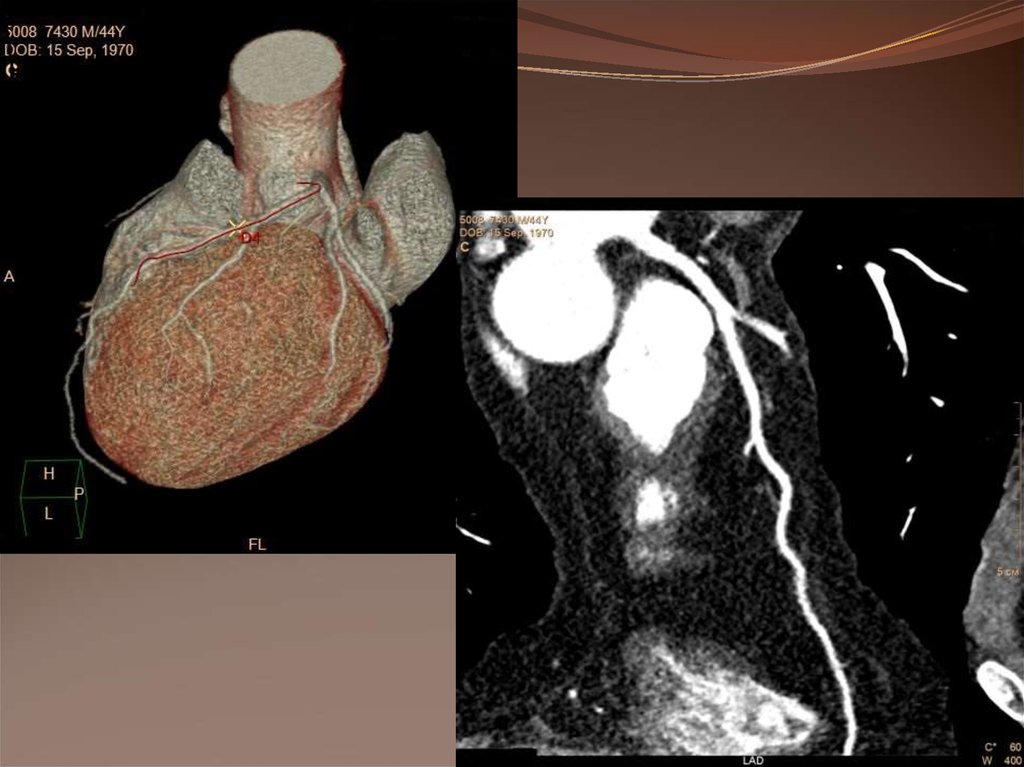

6. Ишемическая болезнь сердца